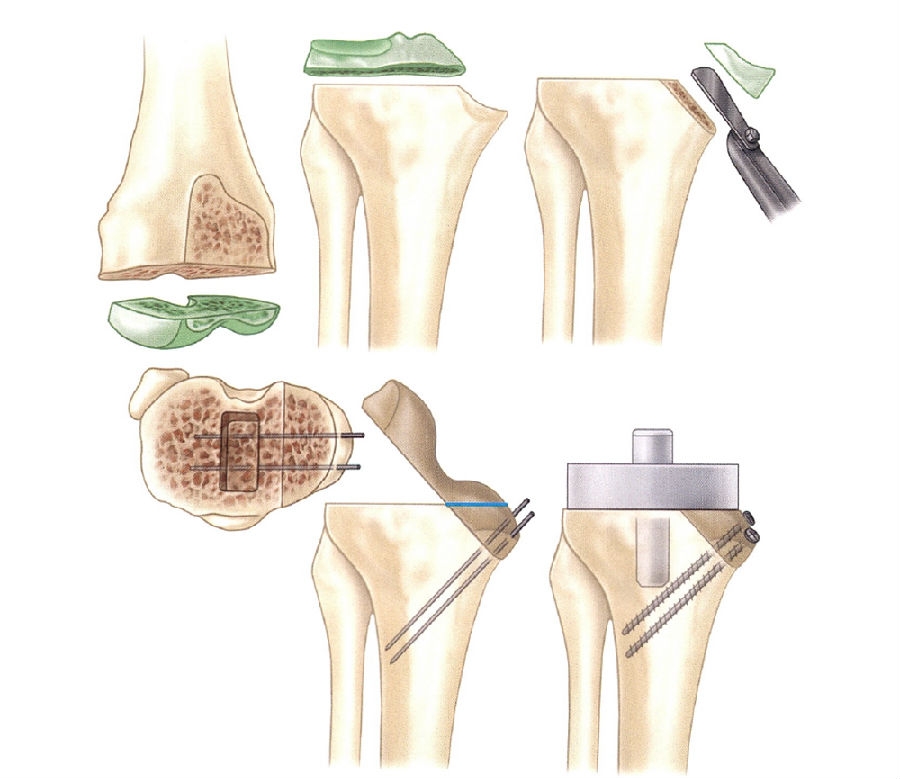

胫骨周围型骨缺损的植骨手术技术:

用骨锯切下尽量少的骨质,将凹陷的、不规则的缺损转变为平整的缺损(图2)。

将自股骨远端或胫骨近端切下的骨块附于平整的缺损处,并用Steinmann针或螺钉固定(图3)。

在胫骨上表面仔细地再次截骨,做出一个平整的表面。

在用骨水泥粘接时,可预先用少量骨水泥封闭移植骨与胫骨的连接部,以防最终用骨水泥固定假体时骨水泥被挤入该间隙内。

若需要从胫骨或股骨上切除过多的骨量才能保证骨面平整对合,则不能采用这种重建方法矫正缺损。在这种情况下,应锉平不规则的骨面,以保证骨移植部位最大限度地对合。

修整移植骨的形状以适应缺损区。

图2 Windsor等处理胫骨边缘缺损的植骨方法

图3 胫骨内侧节段性骨缺损用股骨远端切下的自体骨填充,用松质骨螺钉固定

恢复中立位对线非常重要,这对于移植骨的存活及假体松动均有影响。股骨和胫骨都使用带髓腔柄的假体以保护周边移植骨不受应力影响。